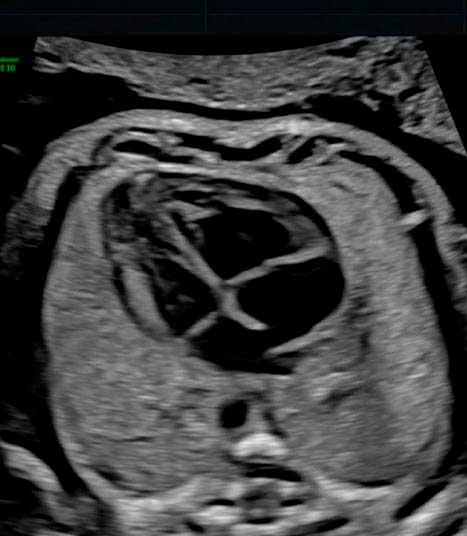

Somos expertos en detección temprana de anomalías. Brindamos una gama completa de Ultrasonidos Fetales y Ecografías 5D-7D: